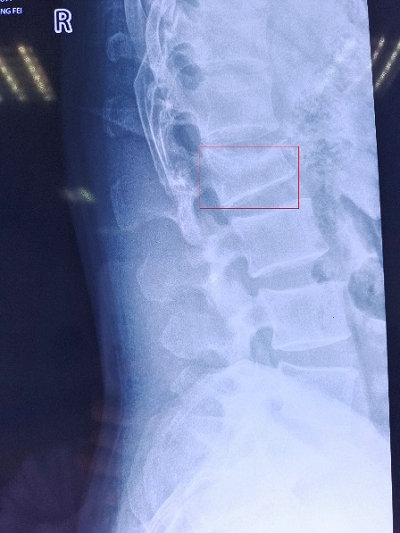

一位41岁中年男性高处坠落后出现腰部疼痛,不敢站立及扭动腰部,遂至郑州大学第五附属医院骨科一病区就诊,入院后迅速完善了X线、MRI等检查(A、B)。骨科一病区徐明杰科主任带领医护团队查房,对患者进行细致查体并查看患者检查结果后指出:患者腰2椎体新鲜压缩骨折(压缩超过1/3),与患者沟通可行“经皮椎弓根钉内固定术”治疗。患者了解到该手术方式不仅创伤小,且可部分恢复椎体高度、减短卧床时间,决定手术治疗。

A.术前X线检查(椎体压缩超过1/3)